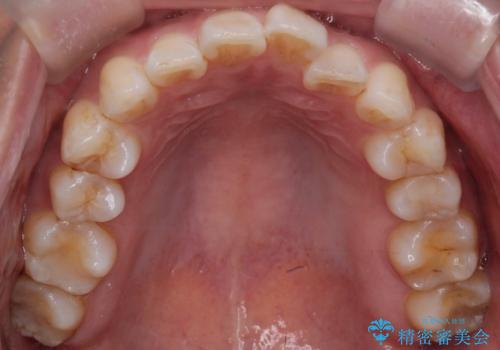

- 「歯のガタつきが気になる」「前歯の真ん中がずれている」との主訴で来院されました。診察の結果、上下の歯列に中等度の叢生(凸凹)があり、特に前歯の位置のずれ(正中の偏位)が目立つ状態でした。見た目だけでなく、かみ合わせにも影響を与える可能性があるため、全体的なバランスの改善が必要と診断しました。

治療はインビザラインを使用し、1~2週間ごとに新しいマウスピースに交換しながら段階的に歯を移動させていきました。特に上下の正中が揃うよう、奥歯や前歯の位置関係に注意を払いながら細かく設計を調整。途中の確認でも、左右のバランスが取れてきたことをご本人も実感されていました。